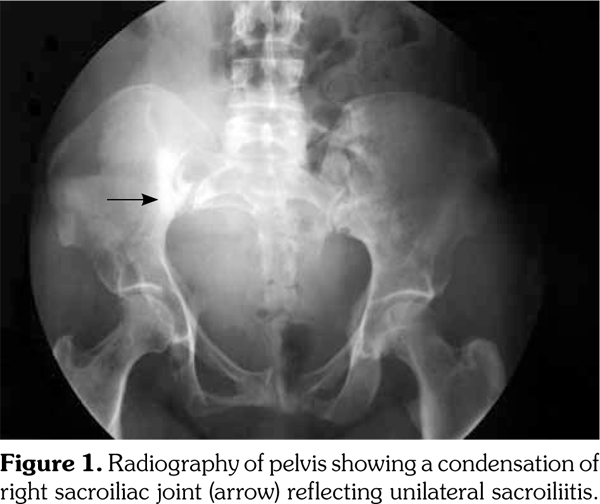

The radiographic exam of the pelvis pointed out a condensation of the right sacroiliac joint reflecting unilateral sacroiliitis (Figure 1). Osseous defects of the sacrum, iliac bones, and right femur were also noted. Pelvis computed tomography scan showed a sacroiliac joint space narrowing associated with sclerosis and microgeodes which might suggest a septic sacroiliitis, particularly of tuberculous or Brucella origin. Multiple bone defects of the sacrum and iliac bones and enlargement of sacral foramina corresponding to multiple neurofibromas (Figure 2) were also noted. Magnetic resonance imaging revealed a juxtaarticular plexiform neurofibroma with massive invasion of the right sacroiliac joint and soft tissue (Figure 3). Tuberculous origin and malignant transformation were both discussed. Sacroiliac biopsy was performed showing histological patterns consistent with NF, with fusiform cells and fibrillary cytoplasm making a typical lemuroid appearance. Patient was referred to surgery.